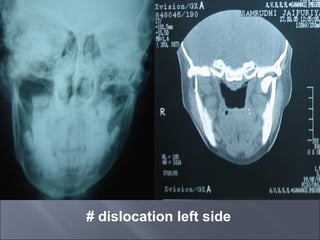

# dislocation left side